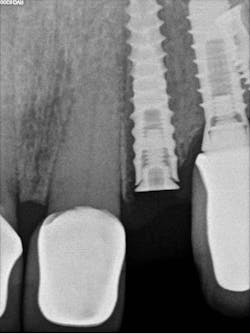

The decision to use the Ditron Implant System was based on the following treatment plan: extraction and immediate implant placement, with immediate provisionalization using a final titanium abutment. Extraction and immediate implant placement with immediate provisionalization have shown to be quite successful.

Maintaining initial stability is important when an implant is placed in a compromised extraction site, since there is less bone-to-implant contact there than in a healed site. Because of its architecture, the Ditron Ultimate implant offers a very high initial stability and strong abutment connection. The implant profile uniformly distributes the stress directly to the bone, which results in a more even distribution of force and lower long-term crestal resorption. This implant system has a good aggressive thread profile and a secure abutment connection, which are both key characteristics. The microthreads on the implant’s reverse conical neck (RCN) greatly increase the implant’s ability to resist axial displacement, and the mechanical stimulus the microthreads provide helps to preserve the peri-implant marginal bone. By inserting an Ultimate implant, 5.57 mm3 of bone will be saved compared to that of a non-RCN implant.7

First visit: Extraction and immediate implant placement, immediate placement of the final abutment prepared intraorally, and then a provisional out of function.